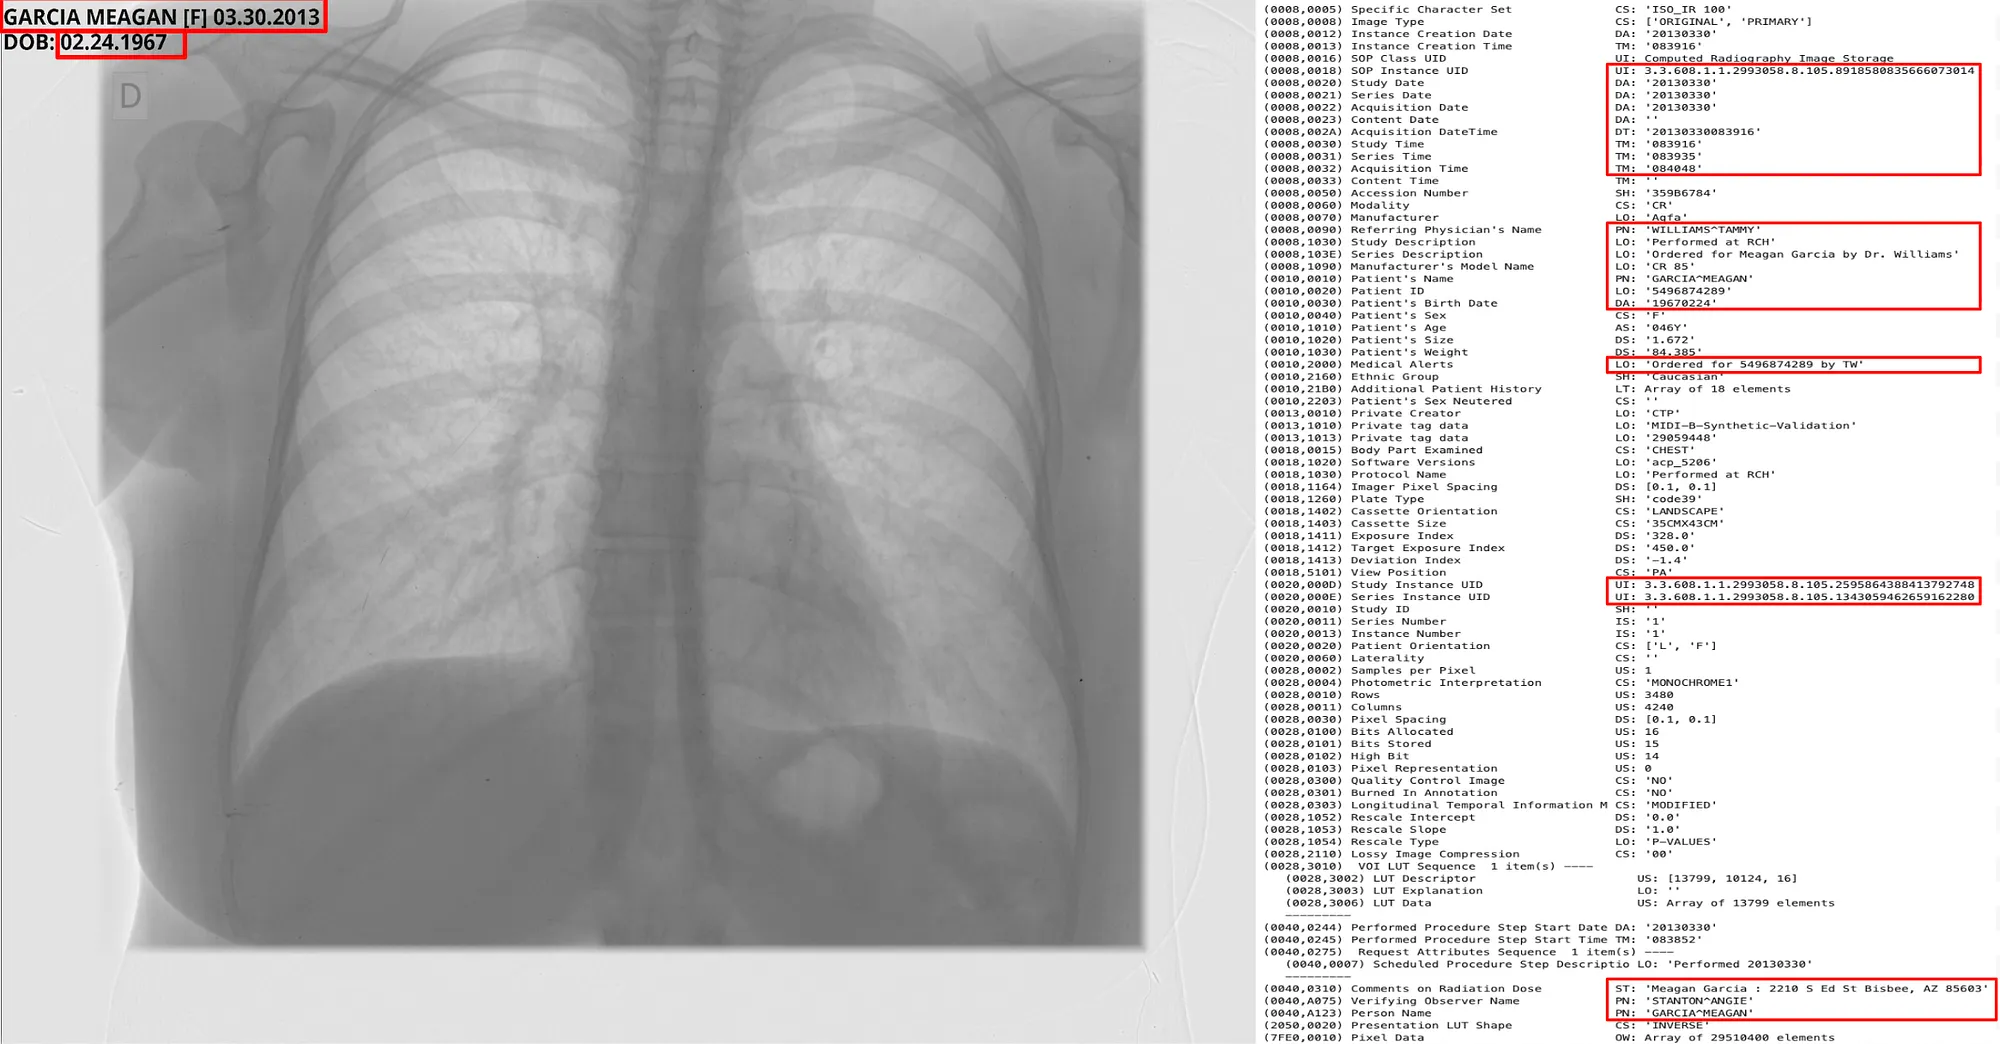

To help you visualise, we will use a sample DICOM file from the MIDIB dataset, which contains PHI in the metadata and Pixels.

Metadata DeIdentification Original ( Left ) -> DeIdentified ( Right )